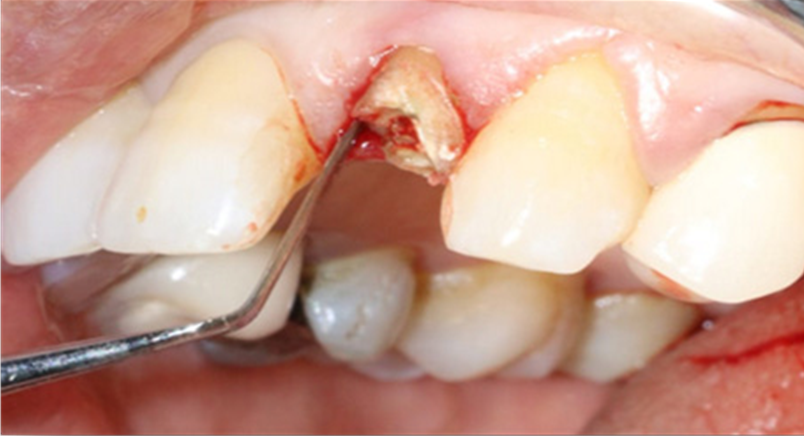

The patient returned for her third appointment, corresponding to the surgical phase of treatment. After disinfecting the incisive-canine area, local anesthesia was administered. The maxillary left lateral incisor (tooth 22) was then atraumatically extracted to preserve the vestibular bone. (Figure 4) Following extraction, the surgical guide was positioned and stabilized, and the drilling sequence was initiated for the placement of a 3.6 mm × 12 mm Biotech implant (Figure 5).

Figure 4: Atraumatic extraction of the 22.